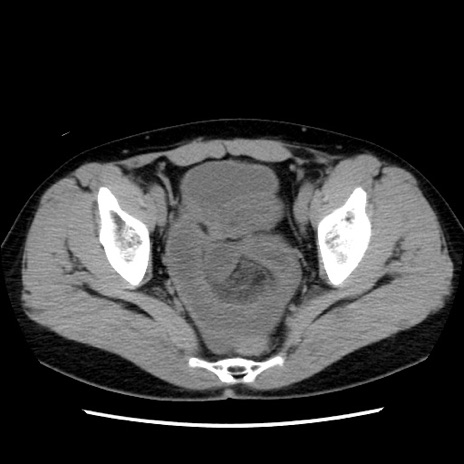

症例10(横断像)

【症例】 50歳代女性

【主訴】 腹痛

【現病歴】前日生レバーを食べた。今朝に排便あり。 昼前に突然発症の腹痛を生じ、当院救急外来を受診した。

【既往歴】 子宮筋腫にてで子宮全摘後

【身体所見】 意識清明、腹部:平坦、軟、下腹部やや左を中心に圧痛・反跳痛あり、筋性防御あり

【データ】WBC 7800、CRP 0.07